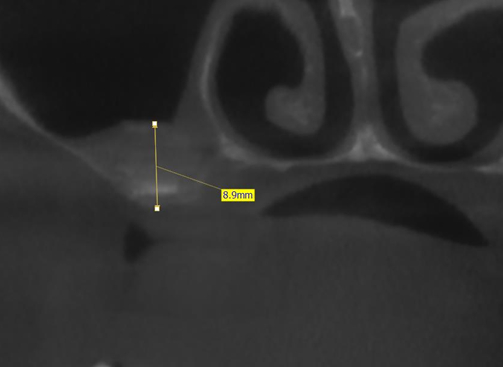

Кстати, рентген только шеи сделали. Голову не стали проверять, хотя он упал прямо на неё и мы об этом говорили, да и по его лицу это было видно.

Посмотрел снимки только. Сказал, что, скорее всего, ушиб. А точнее - потом будут узнавать.